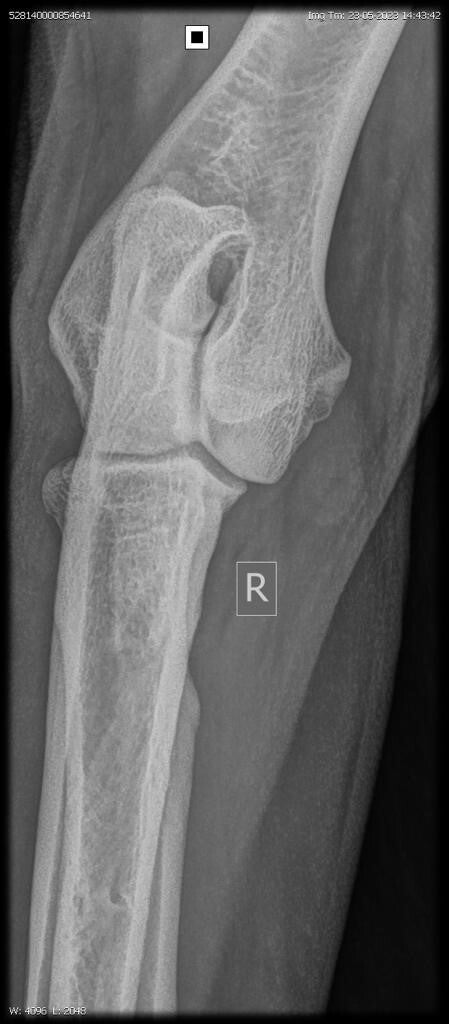

23/06/2023: Röntgenopname ellenbogen + heupen -> geen afwijkingen (heupdysplasie A, ED vrij)